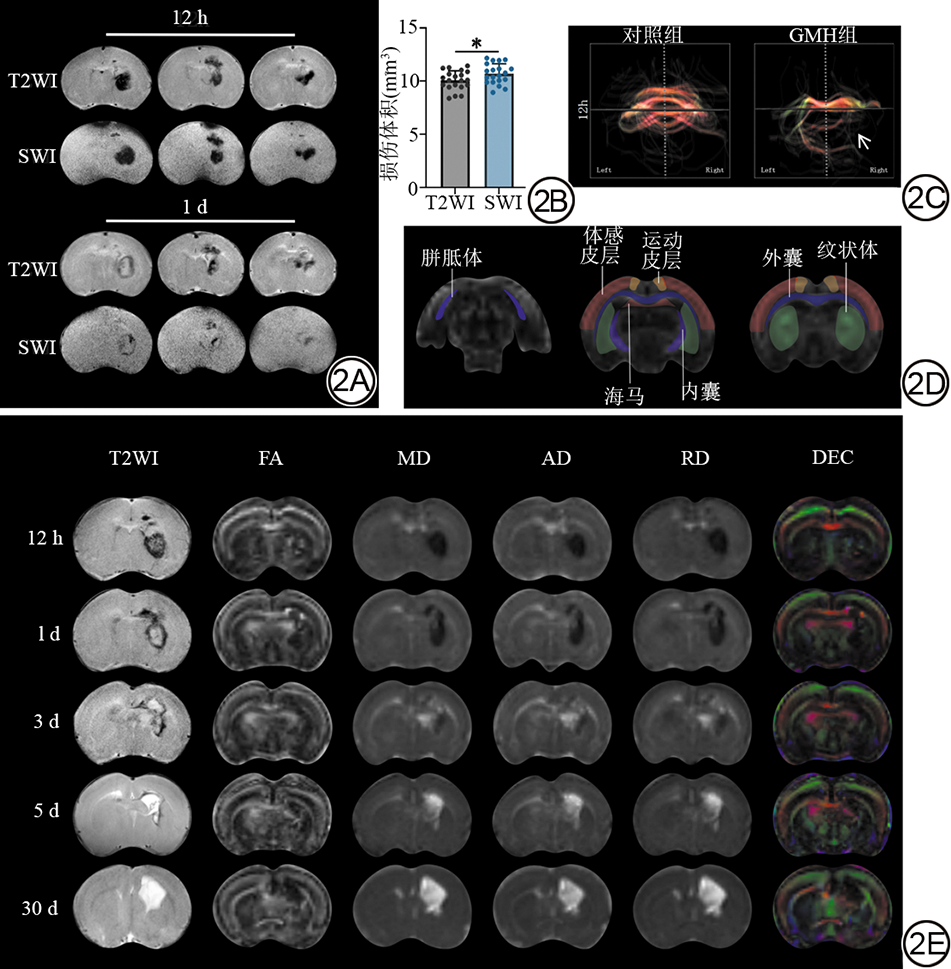

所有成功建模的大鼠在34 d观察期内均存活。术后12 h,20只GMH组新生大鼠T2WI及SWI均显示纹状体区形成边界清晰的低信号血肿。至术后1 d,血肿中心在T2WI出现片状高信号,而SWI上血肿边缘显示模糊(图2A)。术后12 h对血肿体积量化的结果显示,SWI测得的出血体积显著大于T2WI(t=2.085,P=0.044)(图2B),两名医师组内ICC分别为0.921、0.926,组间ICC为0.903,提示SWI检测急性出血的敏感性更高。

白质纤维束三维重建显示,对照组大鼠双侧白质纤维束走行自然、连续且对称,结构完整;GMH组大鼠损伤侧(右侧)纹状体区纤维束出现部分缺失(箭头示)(图2C)。大脑的7个ROI见图2D。纵向MRI追踪发现,血肿区在T2WI上早期呈低信号,随后逐渐演变为高信号,并逐渐突破侧脑室,至GMH后30 d呈均匀高信号。DTI参数中,MD、AD与RD图显示出与T2WI相似的信号演变趋势,而FA图与方向编码彩色图(directionally encoded colormap, DEC)提示损伤侧纹状体区白质纤维方向性紊乱(图2E)。

图2  GMH后早期影像学特征、ROI定位及损伤演变。2A:GMH后12 h及1 d冠状位T2WI及SWI图像示血肿信号演变。2B:GMH后12 h基于T2WI与SWI测量的病灶体积统计(n=20)。2C:GMH后1 d纹状体区白质纤维束三维重建示意图。2D:代表性大脑ROI示意图。2E:GMH后不同时间点T2WI与DTI参数FA、MD、AD、RD和DEC的图像变化趋势。*:P<0.05。GMH:生发基质出血;ROI:感兴趣区;T2WI:T2加权成像;SWI:磁敏感加权成像;DTI:扩散张量成像;FA:各向异性分数;MD:平均扩散率;AD:轴向扩散率;RD:径向扩散率;DEC:方向编码彩色图。

Fig. 2  Early imaging features, ROI localization, and injury evolution following GMH. 2A: Coronal T2WI and SWI at 12 h and 1 d post-GMH, showing signal evolution of the hematoma. 2B: Quantitative lesion volumes measured from T2WI and SWI at 12 h post-GMH (n = 20). 2C: Representative three-dimensional reconstruction of white matter tracts in the striatal region at 1 d post-GMH. 2D: Schematic diagram of representative brain ROI. 2E: Serial images of T2WI and DTI metrics, FA, MD, AD, RD, and DEC, across different time points post-GMH. *: P < 0.05. ROI: region of interest; GMH: germinal matrix hemorrhage; T2WI: T2-weighted imaging; SWI: susceptibility-weighted imaging; DTI: diffusion tensor imaging; FA: fractional anisotropy; MD: mean diffusivity; AD: axial diffusivity; RD: radial diffusivity; DEC: directionally encoded colormap.